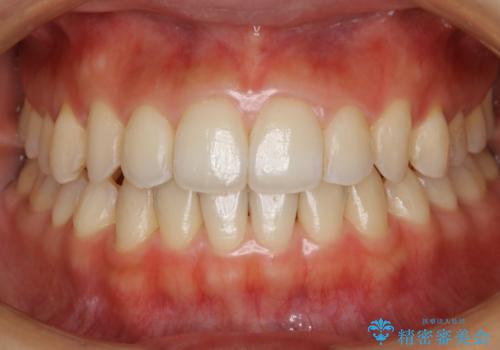

ワイヤー矯正後の後戻り 出っ歯を治したい マウスピース矯正